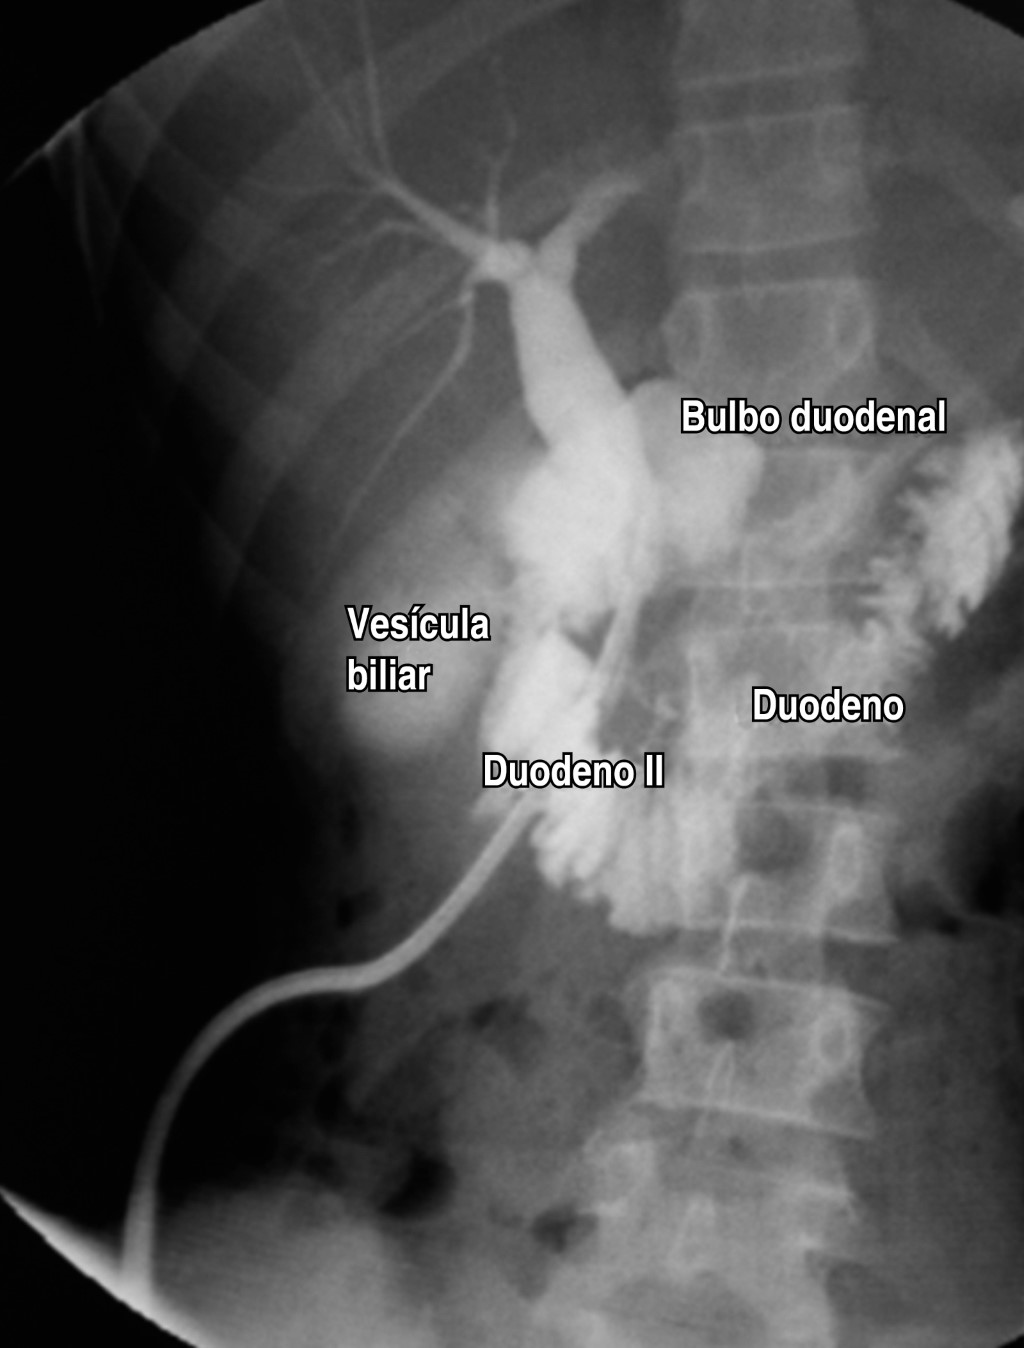

Se realizan estudios de imagen: ecografía abdominopélvica compatible con lesión tumoral heterogénea retroperitoneal con áreas quísticas en la vecindad de la cabeza del páncreas que mide 6 × 10.1 cm por encima del área suprarrenal; tomografía computarizada (TC) de abdomen y pelvis simple y con contraste endovenoso, se evidencia lesión tumoral heterogénea tabicada con captación del contraste en la periferia y tabiques, presencia de áreas de menor densidad quísticas localizada en la cabeza del páncreas de contornos bien delimitados que miden 5.9 × 6.7 × 7 cm; cuerpo y cola pancreática sin alteraciones, sin dilatación del conducto de Wirsung, sin presencia de obliteración de la grasa perivascular en arteria mesentérica superior ni del eje esplenoportal, ni evidencia de adenomegalias retroperitoneales (Figura 1).

La paciente cursó un postoperatorio favorable de 33 días, además de las medidas generales se implementó antibioticoterapia de amplio espectro correspondiente a amikacina 680 mg cada día intravenoso por 10 días acompañado de imipenem 500 mg cada seis horas intravenoso por 15 días, para pasar luego a cefalexina 500 mg por vía oral cada ocho horas por siete días y posterior al alta, cefuroxima 500 mg por vía oral cada 12 horas por cinco días; nutrición parenteral iniciando al tercer día postquirúrgico y manteniéndose por 10 días, al séptimo día postquirúrgico se inició dieta líquida estricta para luego progresarla a dieta blanda que fue bien tolerada y el uso de análogo de somatostatina desde el inicio del postquirúrgico a razón de 4 μg intravenoso cada ocho horas hasta su alta, además de establecerse un control riguroso del dren, realizando el clampleo diario de éste hasta cumplir las 24 horas para luego continuar con el control fistulográfico, mismo que no reportó un stop o fugas, por lo que se decidió el retiro del dren sin mostrar alteración alguna (Figura 5).

Figura 1